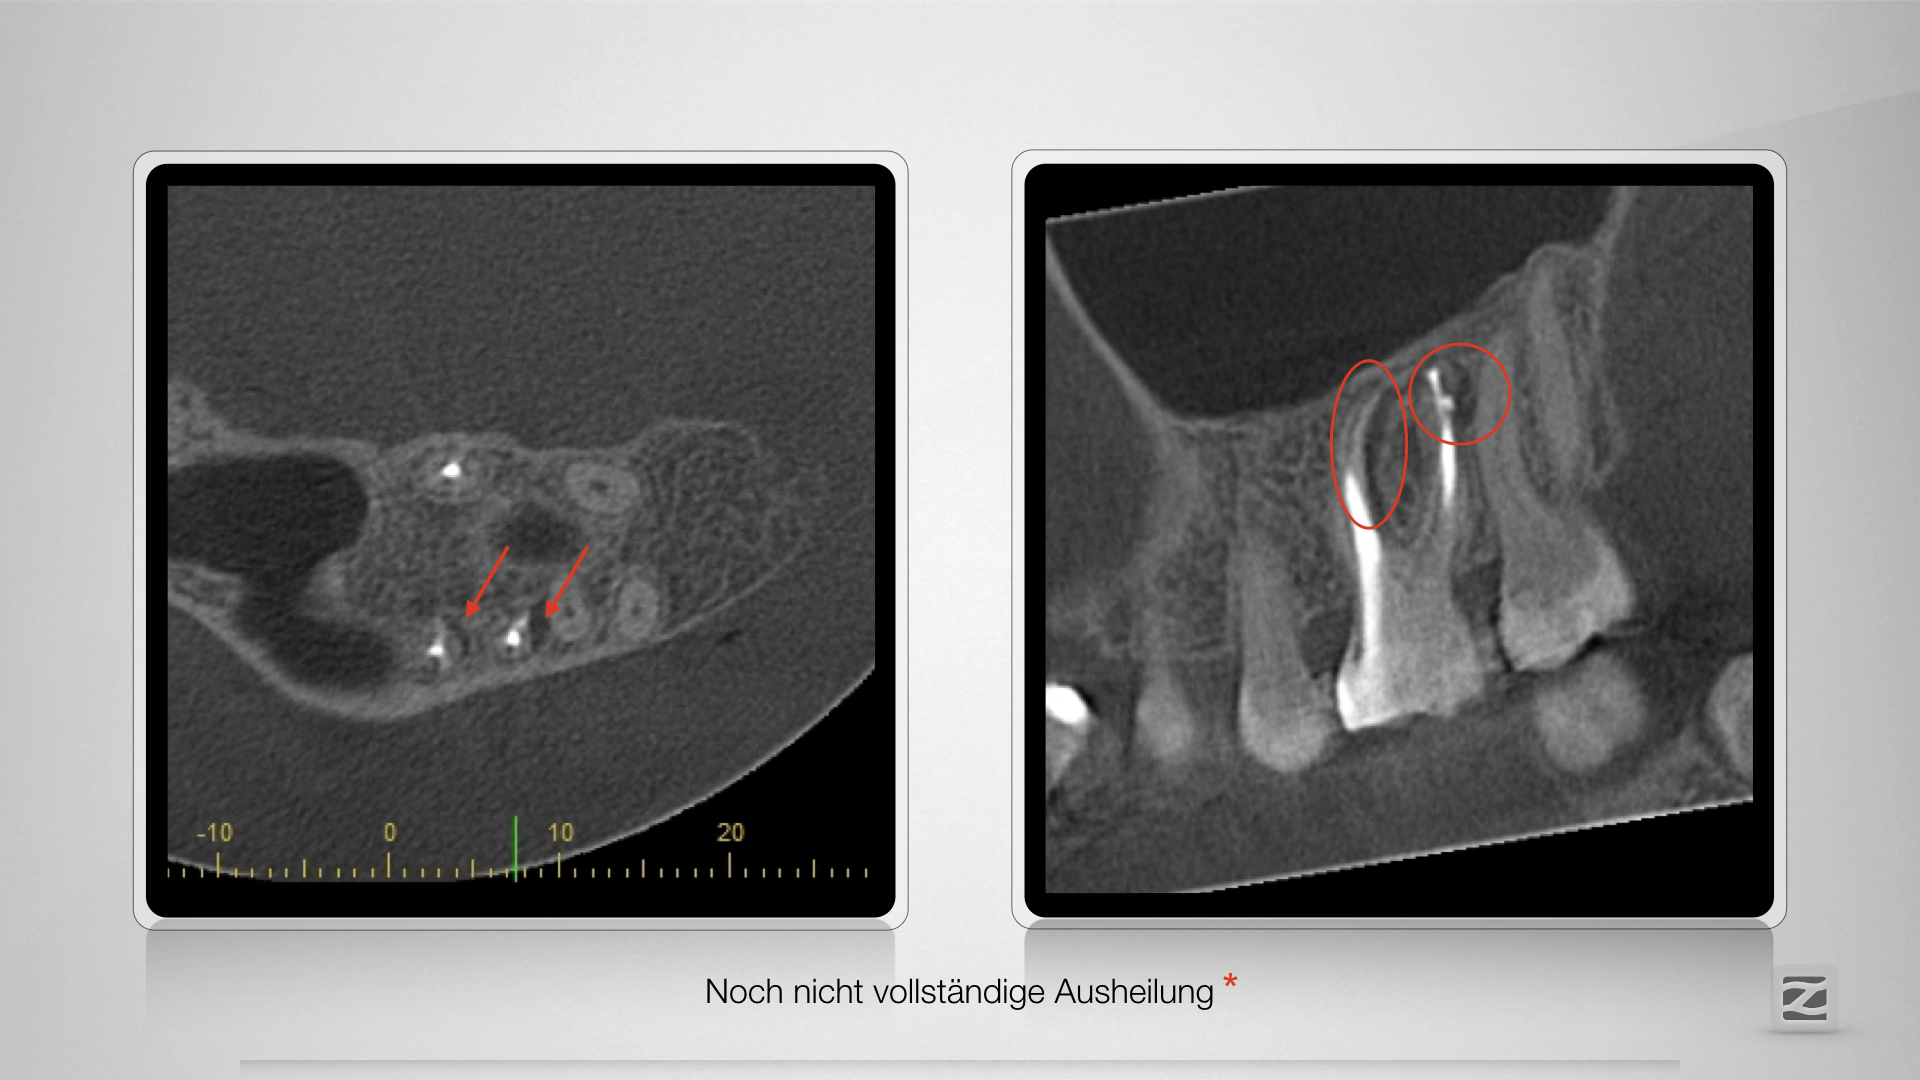

Große Lyse